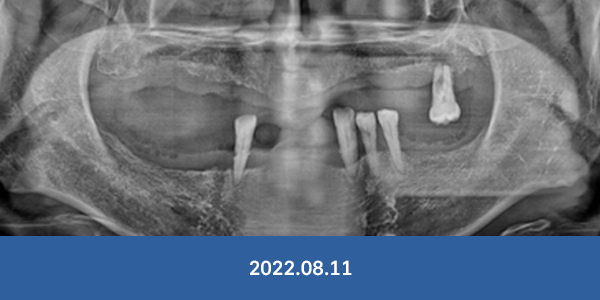

"대학병원 가보랬는데..."

서울감동치과는 가능합니다!

개원 7년간 대학병원 전원율 0% 달성

• 잇몸뼈가 완전히 없는 경우

• 전체 치아가 상실된 경우

• 치주가 심하게 녹은 경우

• 아래턱 신경과 바로 붙은 경우